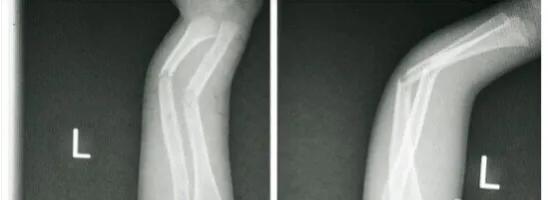

来看看这个3岁的娃娃受伤后的样子,尺桡骨双骨折,前臂已经弯成了快90°,是个父母都要心疼死。

再看看我手法复位石膏固定后的片子,是不是觉得事情又没那么糟糕了呢。孩子回去几周后复查就已经看不到骨折线。